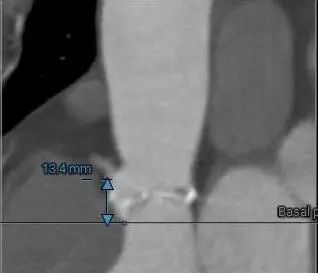

术前CT评估

主动脉根部测量

三叶式主动脉瓣,中重度钙化并增厚,水平夹角45°;LVOT敞口